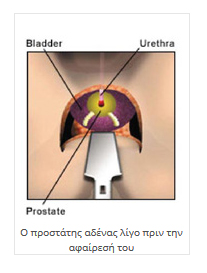

Προστάτης είναι το όργανο που έχει τοποθετήσει η φύση στην πύελο του άνδρα για να γίνεται (χρονικός) διαχωρισμός του σπέρματος και των ούρων και να μην αναμειγνύονται κατά την έξοδό τους από την ουρήθρα.

Τα ούρα παραγόμενα στους νεφρούς, κατεβαίνουν στην ουροδόχο κύστη μέσω των ουρητήρων και συλλέγονται εκεί μέχρι την αποβολή τους από τον οργανισμό (ούρηση). Το σπέρμα παραγόμενο στους όρχεις, μεταφέρεται στις σπερματοδόχους κύστεις και παραμένει εκεί μέχρι τη στιγμή της εκσπερματώσεως. Η έξοδος από τον οργανισμό τόσο των ούρων, όσο και του σπέρματος γίνεται από την ουρήθρα. Επειδή η οξύτης των ούρων καταστρέφει τα σπερματοζωάρια, η φύση τοποθέτησε έναν αδένα που αποστραγγίζει και αλκαλοποιεί το περιβάλλον στο οποίο θα κινηθεί το σπέρμα, από τις σπερματοδόχους κύστεις, μέχρι την έξοδό του από τον οργανισμό και συγχρόνως δεν επιτρέπει την ροή ούρων, μέχρι να ολοκληρωθεί αυτή η διαδικασία. Ο αδένας αυτός λέγεται προστάτης αδένας.

Είναι ένας αδένας που το μέγεθός του εξαρτάται από την ηλικία. Σε έναν άνδρα 40 ετών είναι περίπου 40 γραμμάρια. Από την ηλικία των 60 ετών περίπου, ο αδένας αυτός διογκώνεται γιατί εμφανίζεται η καλοήθης υπερπλασία του προστάτη και λόγω στενώσεως του αυλού της ουρήθρας, δημιουργούνται προβλήματα στην ούρηση.

Μερικές φορές, ανάμεσα στα φυσιολογικά ή τα καλοήθη κύτταρα, δημιουργούνται και αναπτύσσονται (κυρίως στην περιφεριακή ζώνη) και κακοήθη κύτταρα, τα οποία λόγω της αδενικής προελεύσεως δημιουργούν το αδενοκαρκίνωμα του προστάτη.